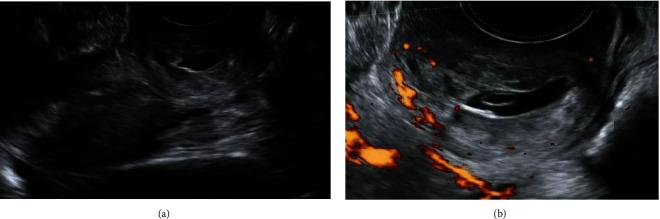

This study is aimed at describing a noninvasive conservative strategy to the treatment of cervical pregnancy and highlighting the success of ultrasound-guided therapeutic techniques. A 43-year-old woman with a history of one previous cesarean section presented in our unit with vaginal spotting and a positive urine pregnancy test. She was diagnosed with a cervical pregnancy, and she was successfully treated conservatively with the administration of intragestational sac methotrexate under ultrasound guidance. Cervical pregnancy is a rare form of ectopic pregnancy that results from conceptus implantation in the cervical canal. The main concern is the associated life-threatening hemorrhage and subsequent need for urgent hysterectomy. The evolution of ultrasound over the past decades has enabled early diagnosis and has shifted the management from a radical surgical approach towards a stepwise conservative therapeutic approach, when possible.

本研究旨在描述一种治疗宫颈妊娠的非侵入性保守策略,并强调超声引导治疗技术的成功。一名有一次剖宫产史的43岁女性因阴道点滴出血和尿妊娠试验阳性就诊于我院。她被诊断为宫颈妊娠,并在超声引导下通过向妊娠囊内注射甲氨蝶呤成功进行了保守治疗。宫颈妊娠是一种罕见的异位妊娠形式,由孕卵植入宫颈管引起。主要问题是可能出现危及生命的出血以及随后需要紧急子宫切除术。在过去几十年中,超声技术的发展使得早期诊断成为可能,并在可能的情况下将治疗方式从根治性手术方法转变为逐步保守治疗方法。